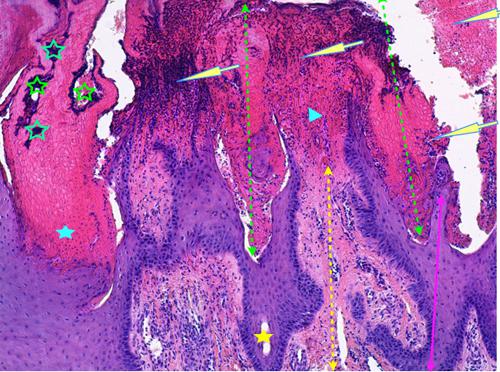

Photo 7 (Hémalun Eosine X 100) peau d’un coussinet : on note une acanthose irrégulière et une hyperkératose de l’épiderme. La couche cornée contient des amas bactériens bleutés. On remarque des zones de nécrose à l’emporte-pièces qui apparaissent comblées d’un matériel fibrino-hémorragique et leucocytaire. Ces zones de nécrose ont un grand axe parallèle à celui des crêtes épithéliales de l’épiderme.

Légendes de la Photo 7 :

- Double flèche verte pointillée : trajets nécrotiques au sein de l’épiderme du coussinet, dont le grand axe est parallèle au grand axe des crêtes épithéliales de l’épiderme

- Double flèche rose : épiderme (grand axe d’une crête épithéliale)

- Double flèche jaune pointillée : derme

- Flèches jaunes : l’épiderme ulcéré et les trajets nécrotiques sont tapissés et remplis d’un matériel fibrino-hémorragique et leucocytaire

- Étoiles vertes évidées : colonies bactériennes cocciformes

- Pointes de flèche turquoises : ulcération de l’épiderme

- Étoiles turquoises pleines : couche cornée parakératosique

- Étoiles jaunes pleines : lumière du canal excréteur d’une glande sudorale atrichiale du coussinet (portion intra-épidermique du canal)